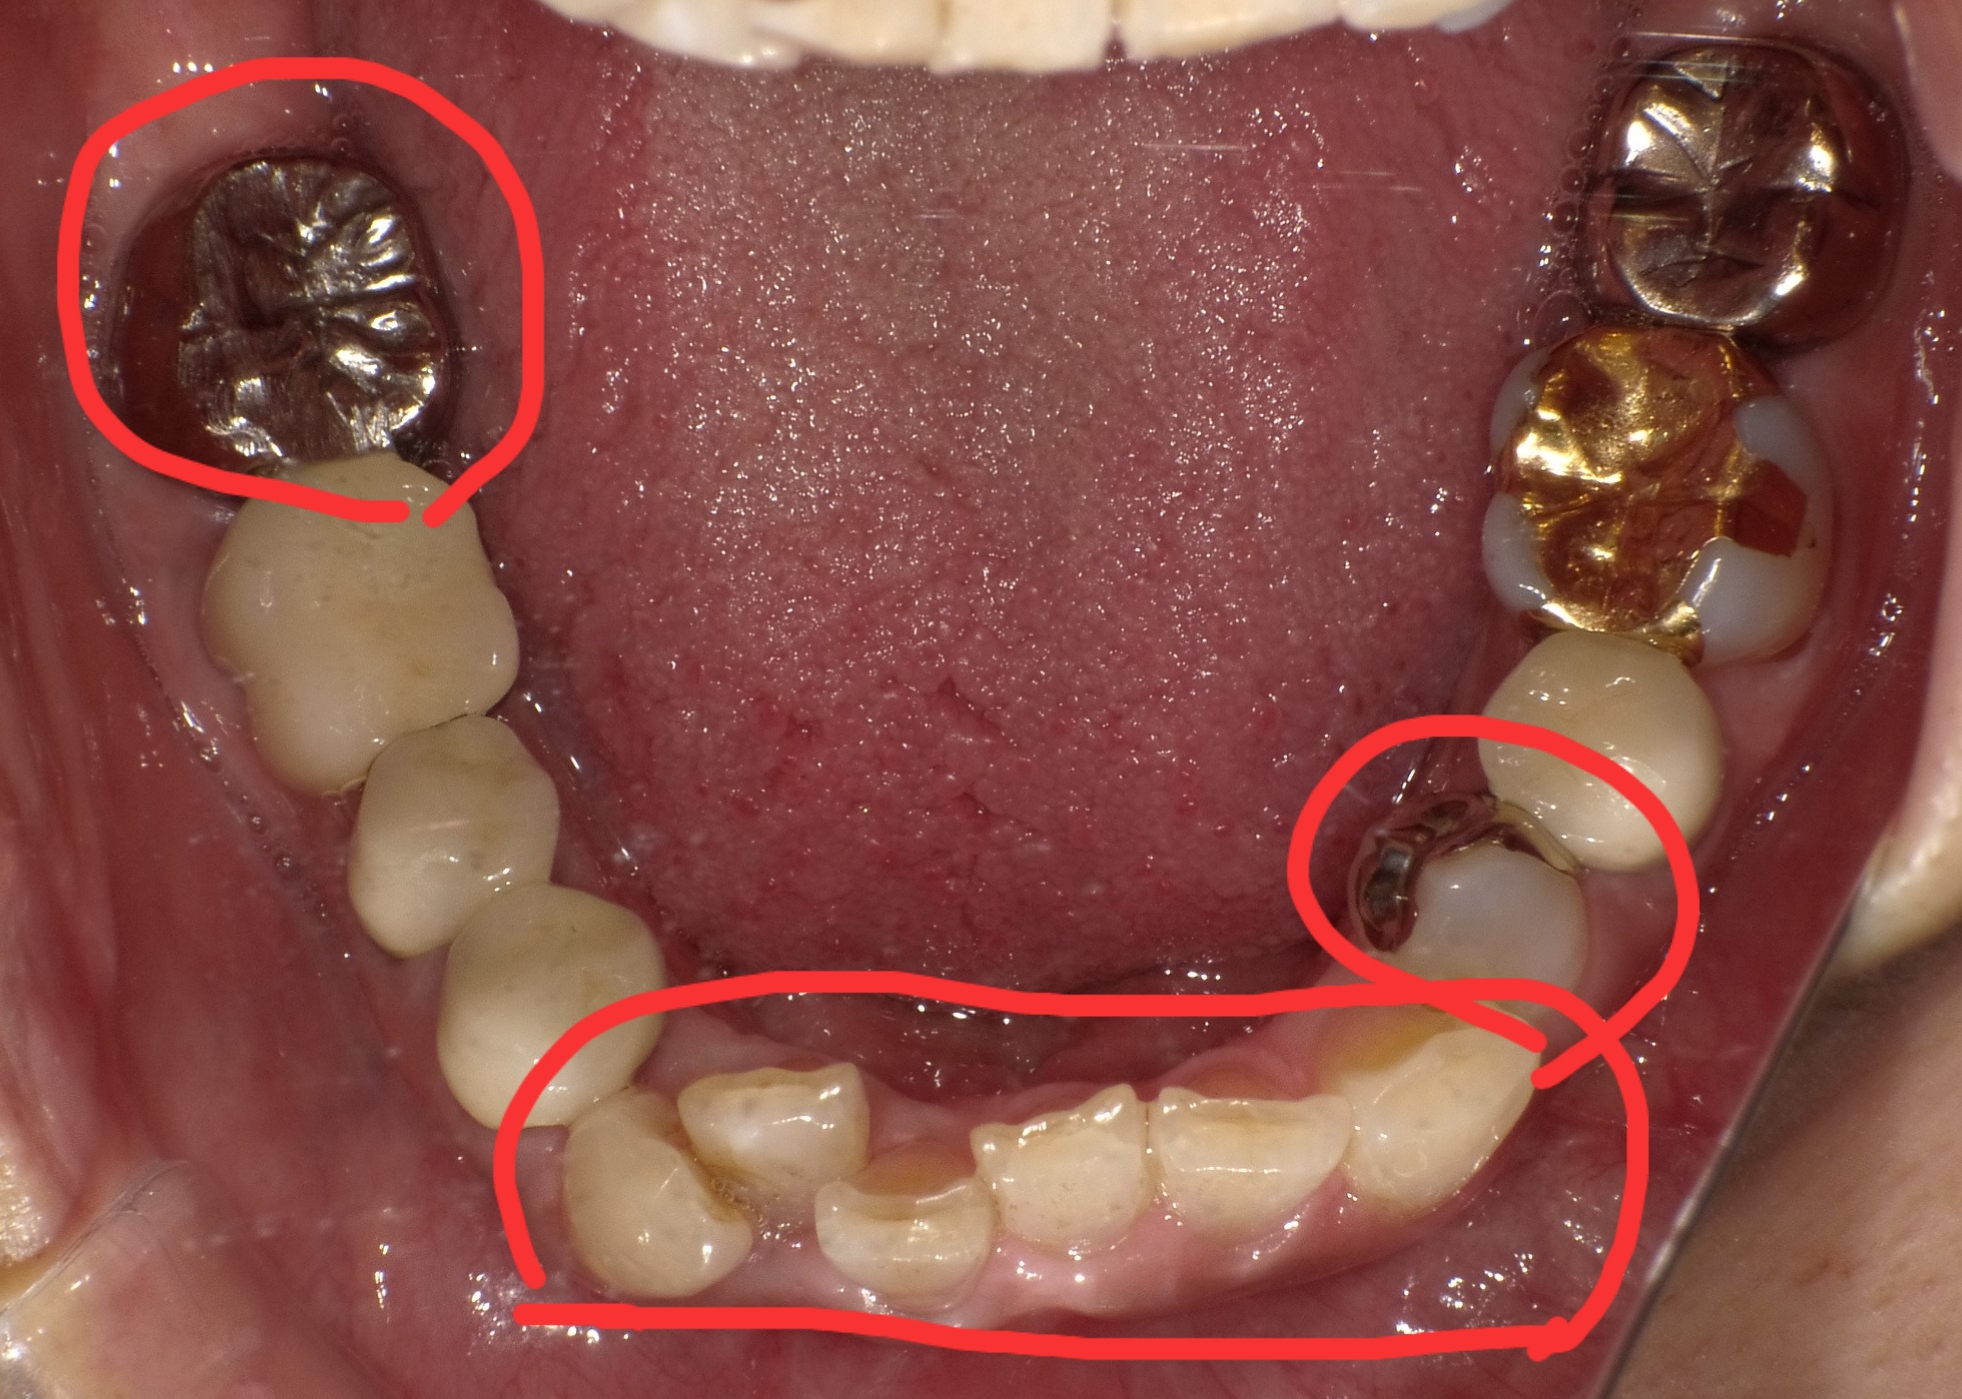

下の写真は治療前と治療後の写真です。

前歯の歯並びと銀歯を白いセラミックに治しました。歯並びは部分矯正で綺麗に並び手前の歯の銀歯は保険の白い詰め物をして奥の歯はセラミックが入りました(*^_^*)部分矯正は3~4ヶ月で下の写真のように綺麗に並んできます!